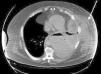

Varón de 49años, fumador, obeso mórbido y con diabetes mellitus tipo2 con mal control terapéutico, que consultó por traumatismo contuso costal izquierdo por la embestida de un toro que causó varetazo sobre dicha región 30días antes de su ingreso en el hospital, no acudiendo a los servicios de urgencias en el momento del traumatismo. Presentaba un hematoma en la pared costal izquierda y dolor torácico, sin mejoría con analgesia habitual. A su llegada a urgencias presentaba presión arterial de 140/86mmHg, frecuencia cardíaca de 110 lpm, saturación de oxígeno del 96% y temperatura de 36,5°C. En la exploración física presentaba hematoma en la pared torácica lateral izquierda sin celulitis perilesional y disminución del murmullo vesicular en el hemitórax izquierdo. En la analítica destacaba una leucocitosis de 32.400/mm3 con neutrofília (92,2%), hemoglobina 10g/dl, glucemia 487mg/dl y proteínaC reactiva 40,3mg/dl. En la radiografía de tórax se apreciaba derrame pleural izquierdo sin objetivarse fracturas costales. Se completó el estudio mediante tomografía computarizada (TC), donde se observó derrame pleural izquierdo que comunicaba con una colección anterolateral izquierda de la pared torácica (fig. 1). Se decidió iniciar tratamiento antibiótico empírico con piperacilina/tazobactam (4/0,5mg i.v. c/8h) y realizar drenaje de ambas colecciones mediante punción percutánea de la colección de la pared torácica y el tubo de tórax, con salida de abundante material purulento. Mediante control radiológico se evidenció adecuada reexpansión pulmonar. Tras 72h de ingreso se objetivaron múltiples orificios en la pared torácica lateral izquierda, con áreas necróticas y purulentas a su alrededor, sin afectación muscular, por lo que se realizó desbridamiento y lavado bajo anestesia general. El resultado microbiológico, tanto del líquido pleural como del absceso torácico, fue positivo para Streptococcus agalactiae sensible al antibiótico prescrito. El paciente permaneció hospitalizado durante 40días, durante los cuales se continuaron las curas de las heridas quirúrgicas sin precisar otros tratamientos quirúrgicos adicionales.

La localización más frecuente de un empiema necessitatis es, como en este caso, la pared torácica anterior, entre la línea medioclavicular y la axilar anterior. Otras localizaciones, descritas con menor frecuencia, son la pared abdominal, el espacio paravertebral, el mediastino, la mama o el diafragma1,2. Antes de la era de los antibióticos la mayoría de los casos estaban causados por Mycobacterium tuberculosis y presentaban una mortalidad del 66%. Con el tratamiento antibiótico ha disminuido significativamente su incidencia, además de cambiar el agente etiológico a expensas de Actinomyces israelii, Streptococcus pneumoniae, Staphylococcus aureus o Pseudomonas cepacia3,4. En nuestro caso se trataba de Streptococcus agalactie y era secundario a un traumatismo torácico, ambos aspectos poco frecuentes en estas circunstancias. La presentación clínica puede ser muy variada, incluyendo dolor torácico, masa en partes blandas, tos o disnea. En función de la edad del paciente y de su morbilidad puede evolucionar hacia shock séptico. En nuestro caso se trataba de un paciente obeso y diabético con mal control terapéutico, ambos hechos favorables para el desarrollo de infecciones de localización y etiología atípica como consecuencia de las alteraciones del sistema inmunológico frente a microorganismos invasores, principalmente hongos y bacterias. Su diagnóstico se basa en pruebas de imagen, principalmente la TC, que demuestra la continuidad entre la colección pleural y el absceso de la pared torácica. El diagnóstico diferencial se debe realizar con otras patologías, como linfomas, mesotelioma o endocarditis5. Aunque el tratamiento de cada paciente debe ser individualizado, son fundamentales tanto el tratamiento antibiótico ajustado al antibiograma cuando sea posible, como el drenaje quirúrgico, este último imprescindible para evacuar el contenido purulento acumulado y conseguir la esterilización y la obliteración de la cavidad pleural, permitiendo así una buena movilidad pulmonar. Para ello podemos emplear distintos procedimientos, como los sistemas de drenaje cerrado mediante un tubo de toracostomía o costectomía parcial, o sistemas abiertos mediante una toracostomía abierta, creando una fístula pleurocutánea que permite el drenaje sin necesidad de tubo. No está establecido el tiempo necesario para ambos tratamientos, pero es recomendable mantener el antibiótico durante una semana por vía intravenosa y continuar entre 1-3 semanas por vía oral, en función de la respuesta clínica del paciente5. Con la asociación de ambos tratamientos se consigue una elevada tasa de curación, con escaso índice de mortalidad (menor del 5%), que suele ser secundaria a la confluencia de varios mecanismos como la insuficiencia respiratoria, la insuficiencia cardíaca, la mediastinitis, la diseminación hematógena o la insuficiencia renal1.